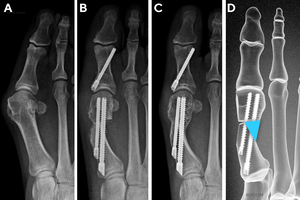

First Metatarsal Regeneration Type II: Callus formation located medial and lateral to the MI anchor bone screw (Figure 3).

_type_ii.jpg)